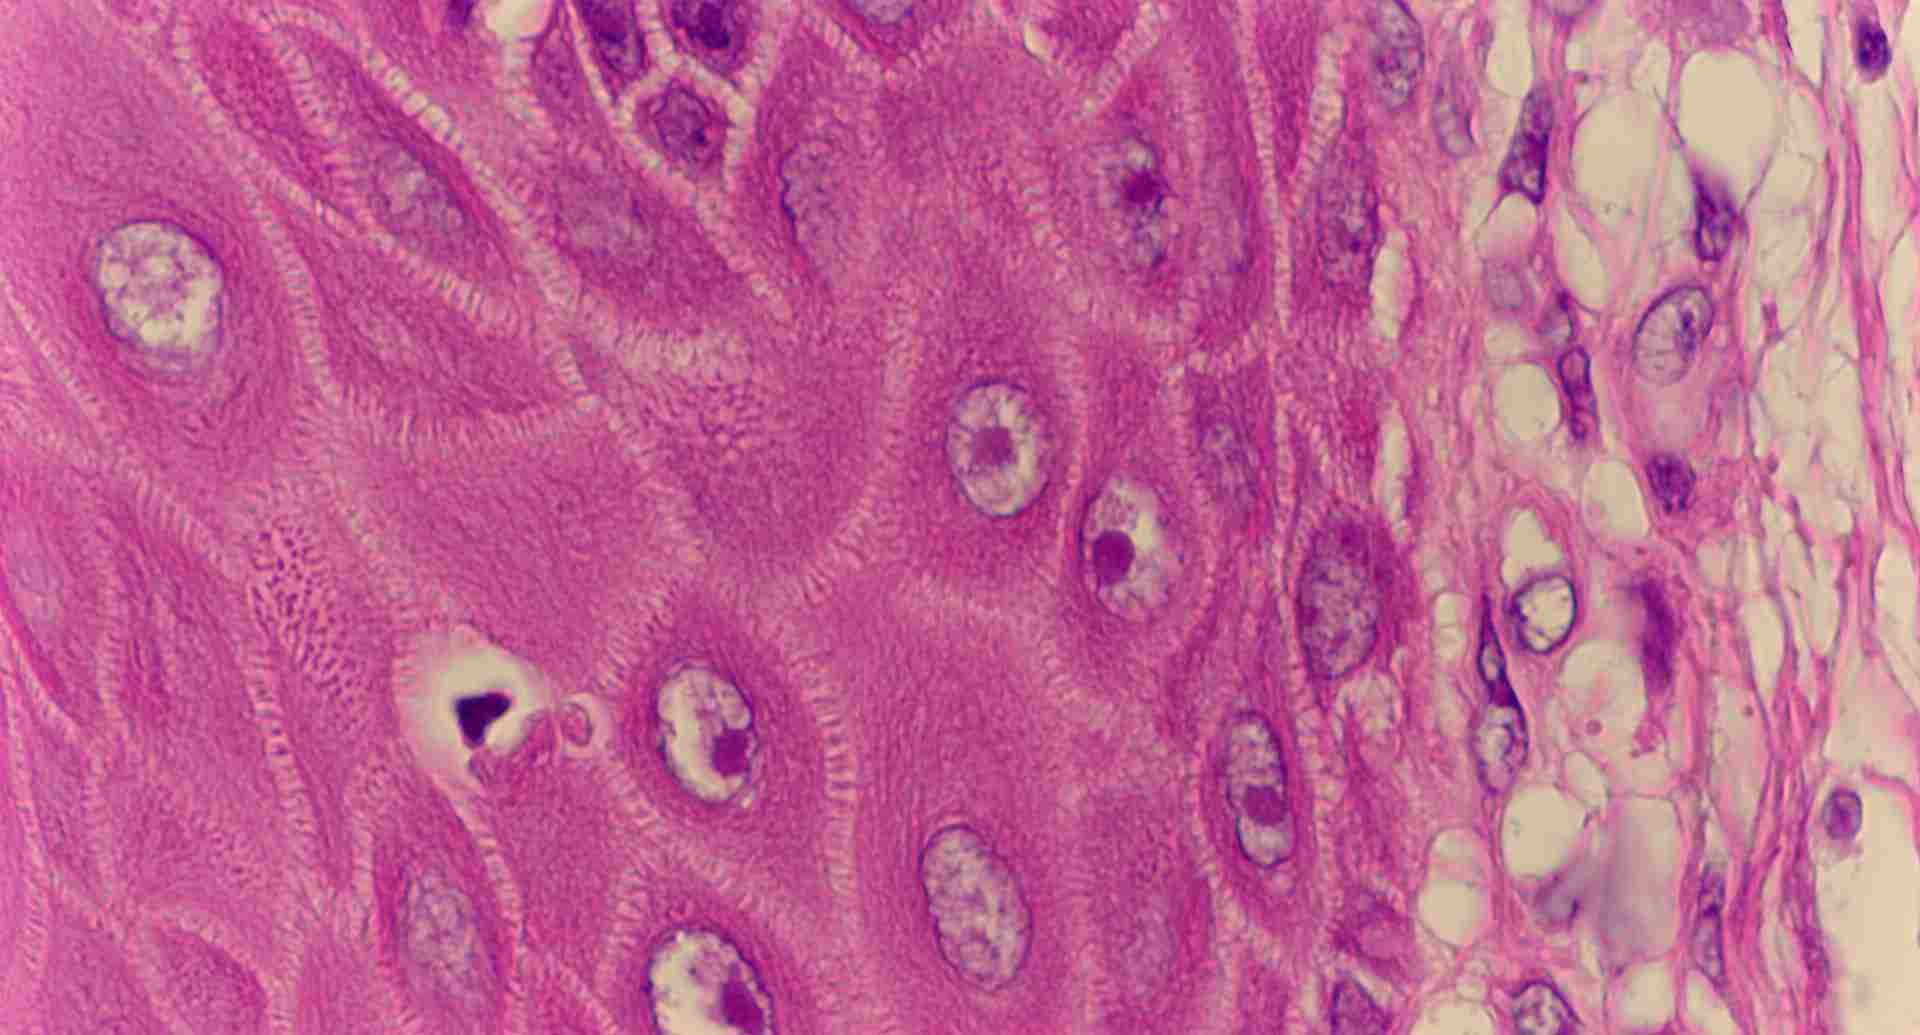

標本6

標本6(94KB)

標本6の説明